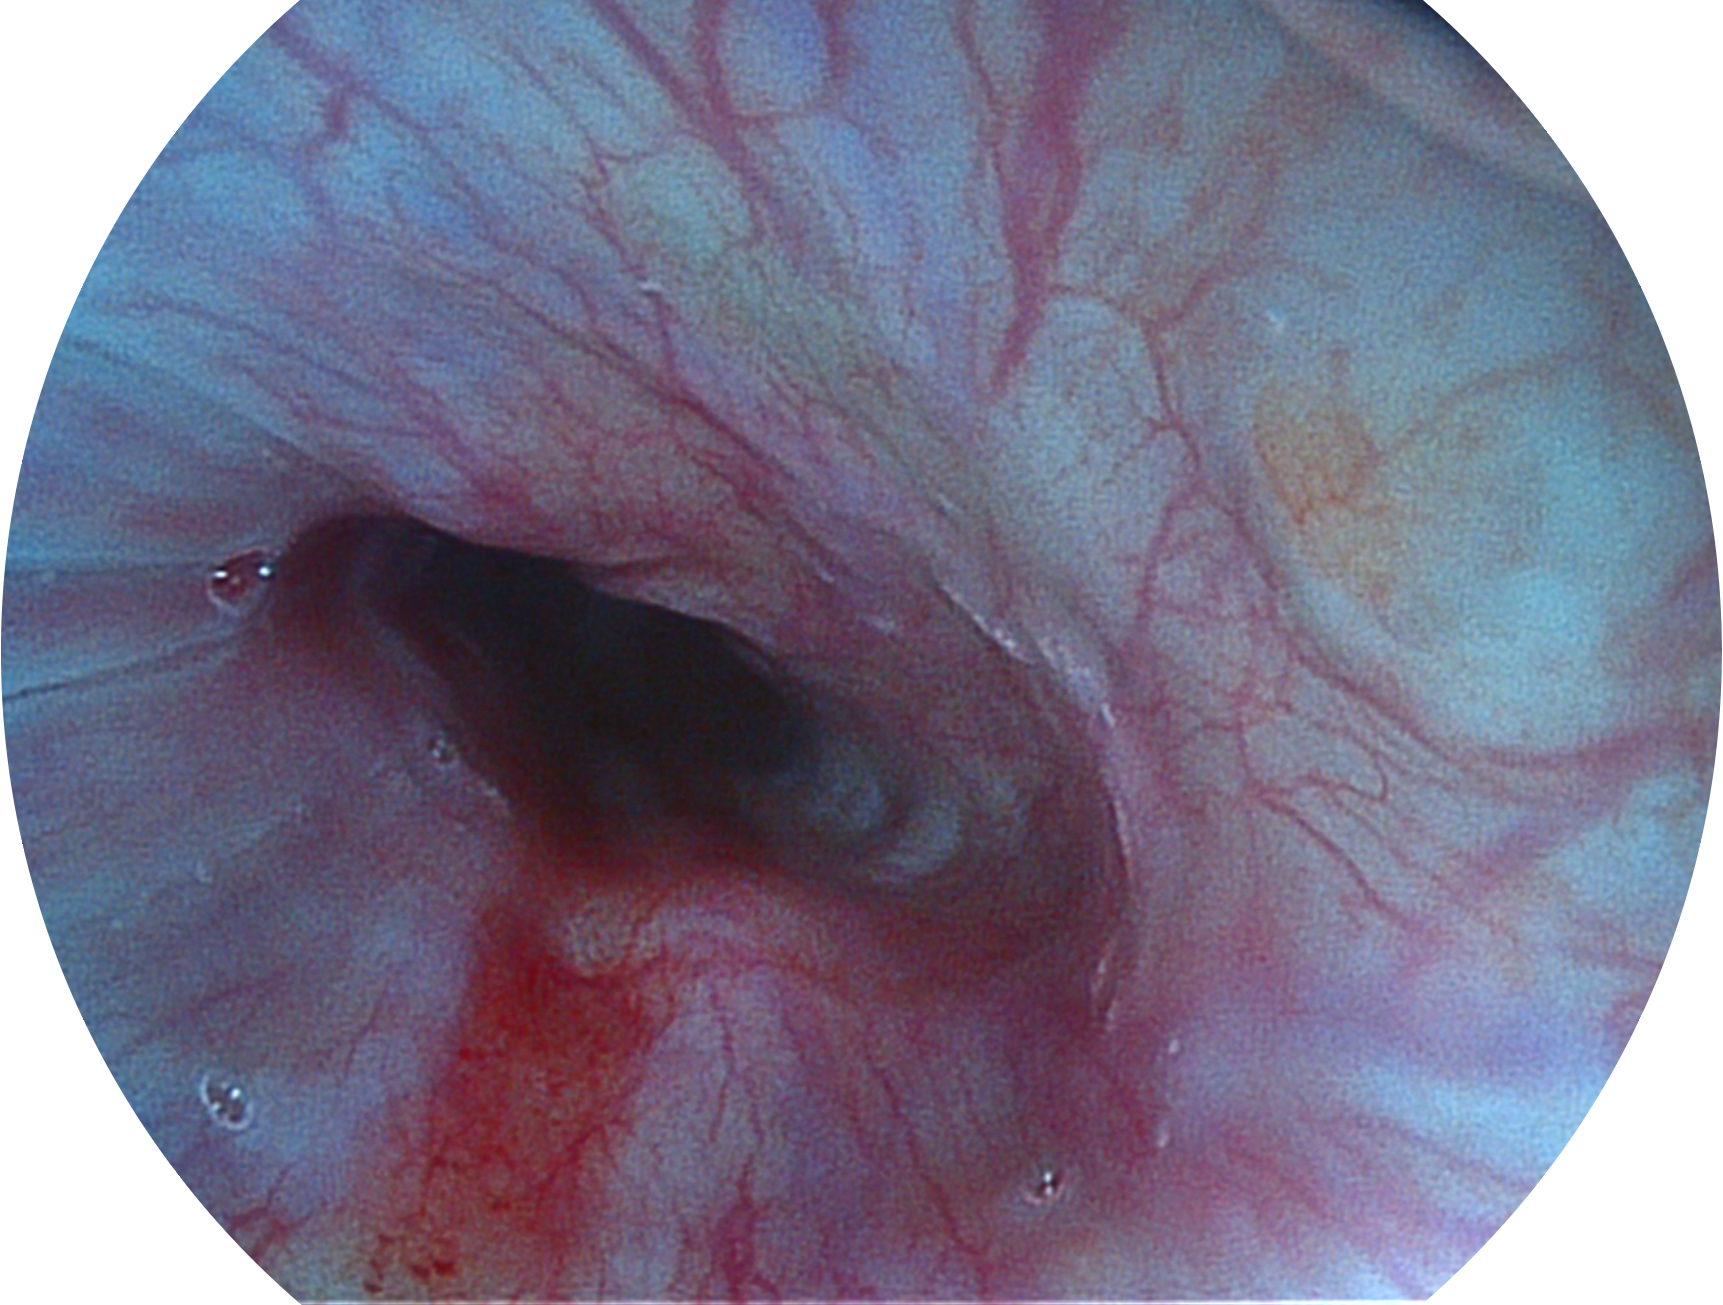

美狮贵宾会官网新开发的内镜染色技术,主要是基于多波长LED 光源的开发,VLS-55Q 四波长LED 光源是由四个不同颜色的LED光按照相应照明模式所规定的特定发光比例进行合束后形成,合束后形成的照明光的光谱由红光、绿光、蓝光及蓝紫光这四个不同的波段范围构成。具有更高光谱自由度,通过光谱比例的控制,实现了聚谱成像技术,英文全称为“Spectral Focused Imaging, SFI”,缩写为“SFI”和光电复合染色成像技术,英文全称为“Versatile Intelligent Staining Technology, VIST”,缩写为“VIST”。